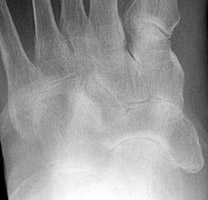

Gout Gout: Large erosion with overhanging edges 1st metatarsal

++